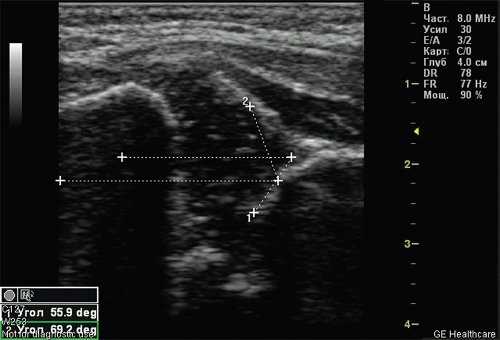

Тип 2а тазобедренных суставов (рис. 3) диагностирован у 46 (11,6%) детей. Это вариант физиологической задержки развития тазобедренных суставов у детей в возрасте до 12 нед, при котором угол α меньше 59°, но больше 50°, соответственно угол β больше 60°.

Рис. 3. Тазобедренный сустав тип 2а.

1 - угол α=55,9°;

2 - угол β=69,2°.